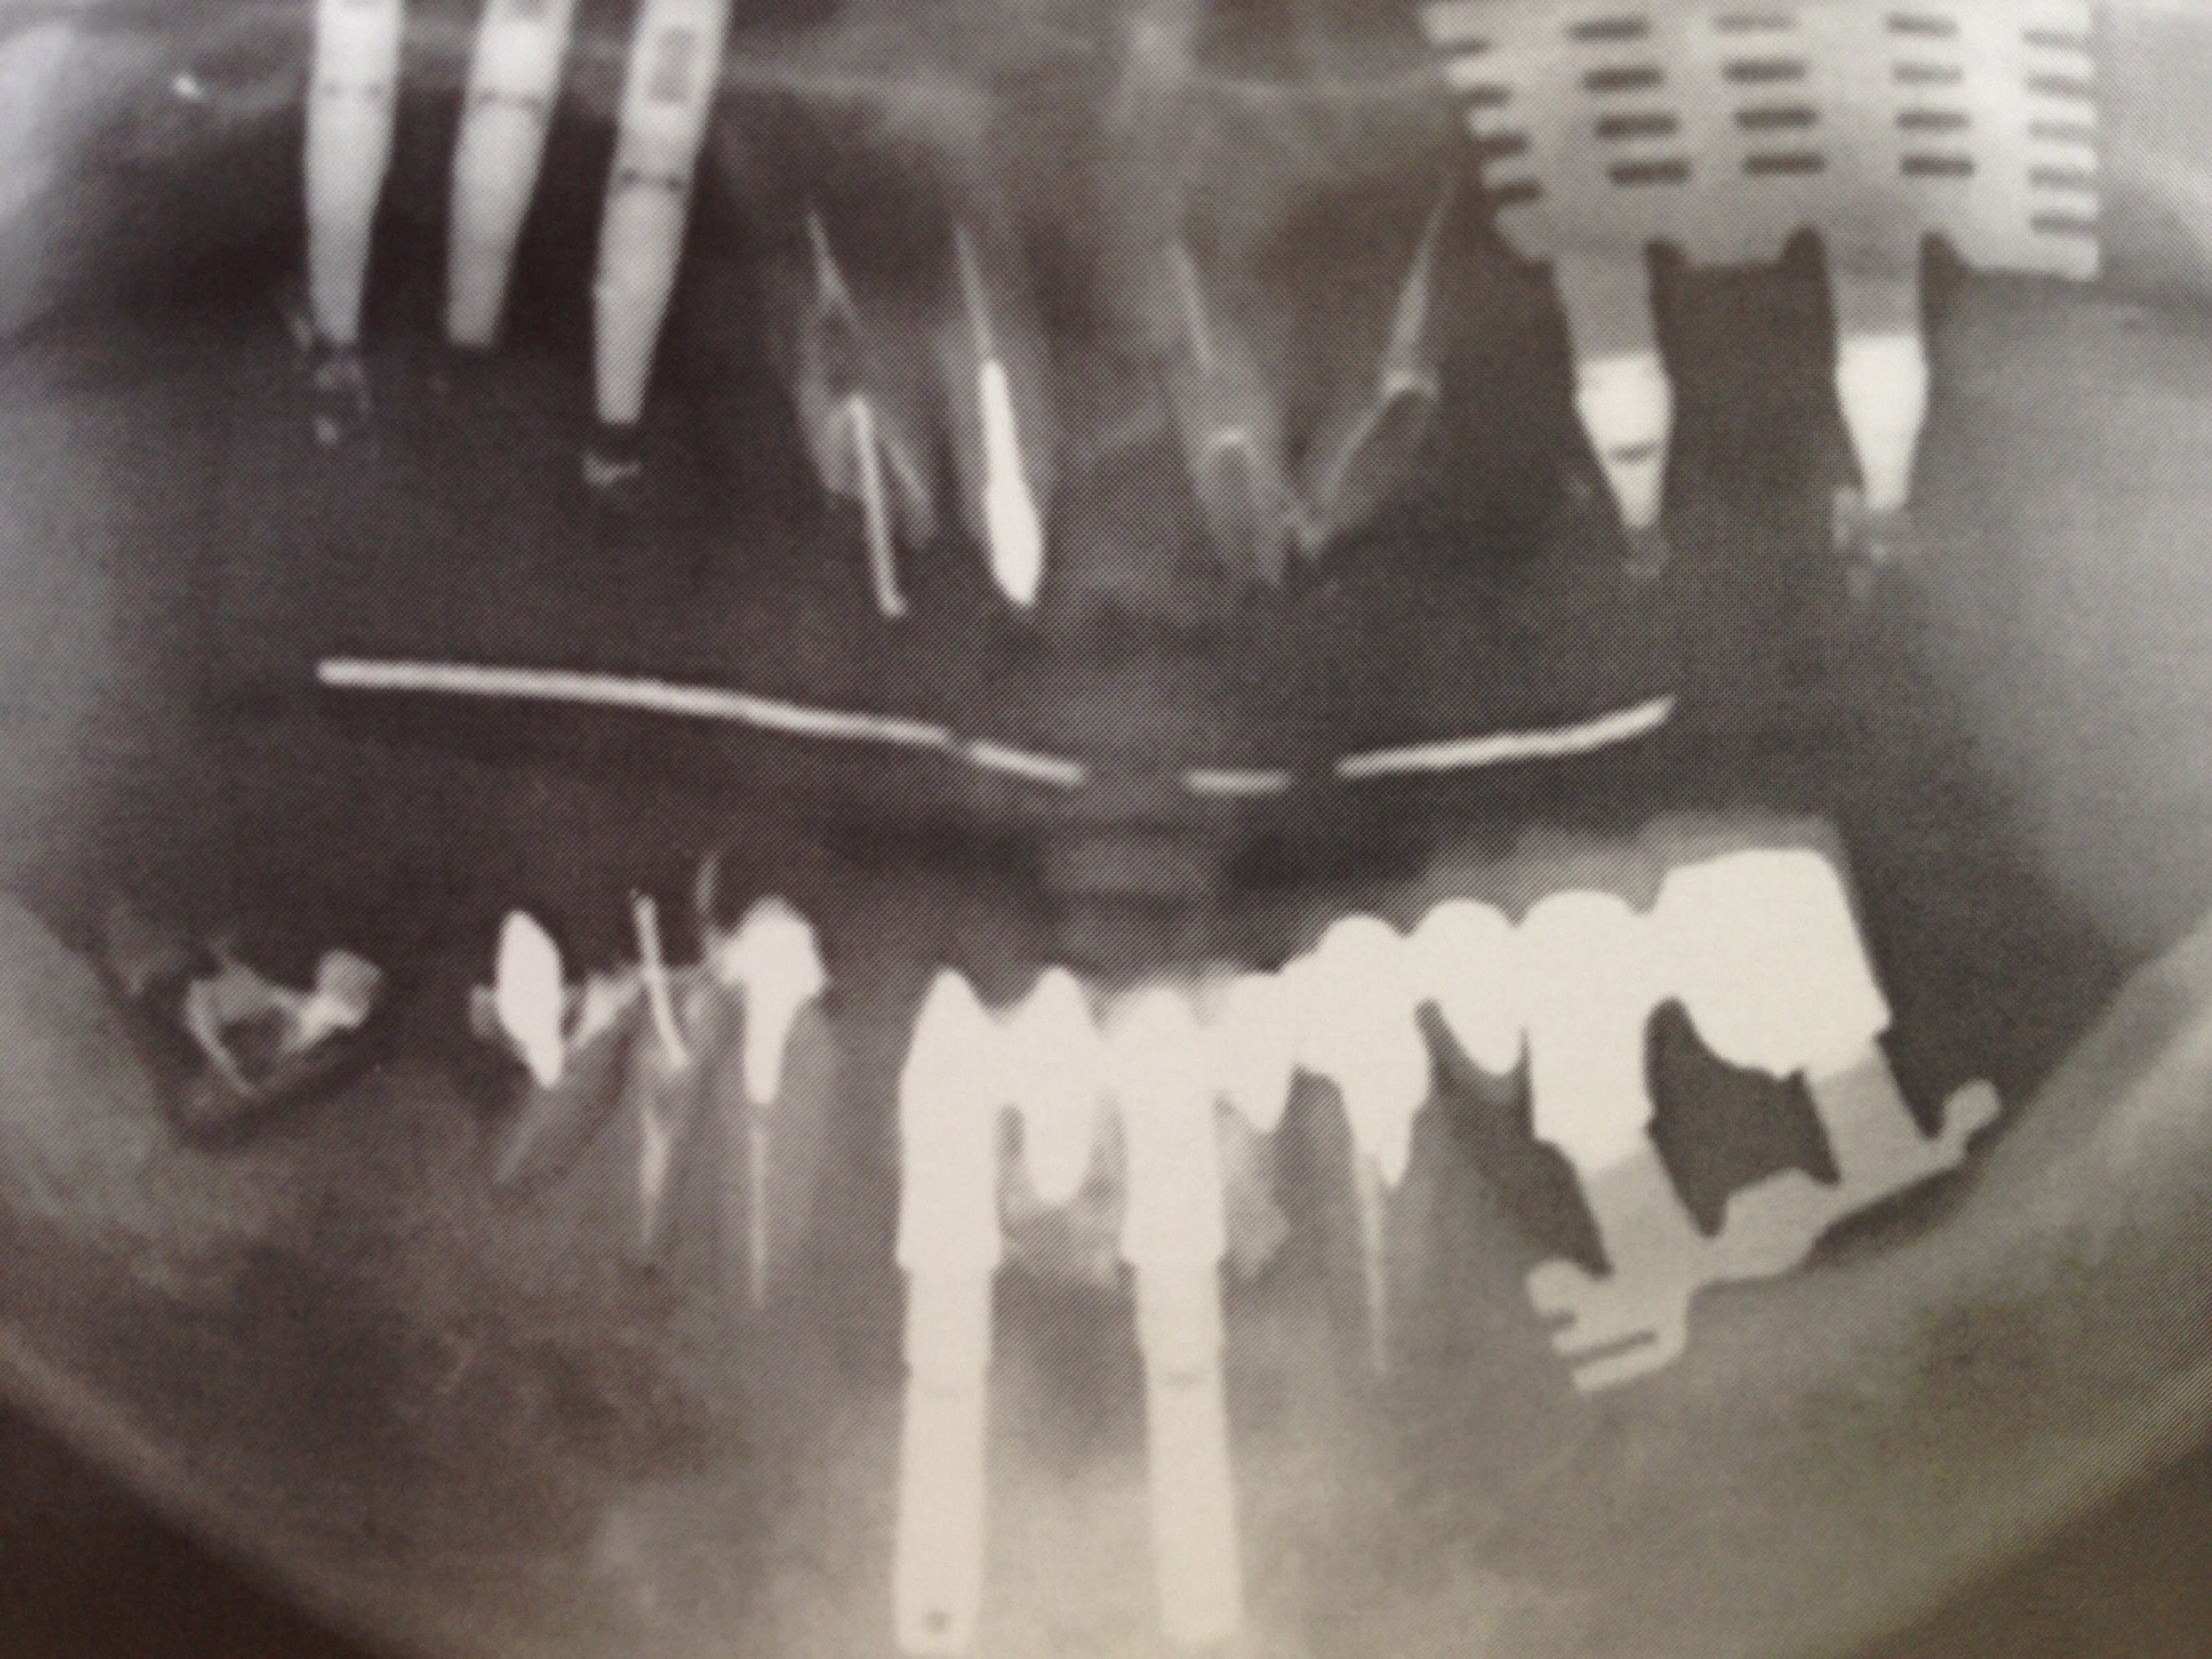

et Le clou du spectacle :

- Implants coquillages tolérés par l'os sous l'Úre Maya

- bridge en or sous l'époque des pharaons

- bridge avec ligature en or sous l'époque romaine

tout ça posé avant 90....

28 ans pus tard